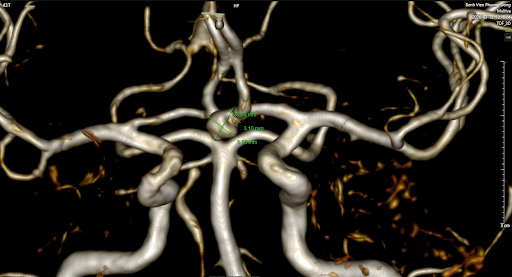

Bệnh nhân nam trẻ, 43 tuổi, hoàn toàn khỏe mạnh, đi khám sàng lọc đột quỵ tại BVĐK Phương Đông. Các chuyên gia tại khoa CĐHA đã phát hiện túi phình động mạch não kích thước ~ 7mm, nếu không được phát hiện và điều trị, túi phình này có thể vỡ và gây đột quỵ, để lại hậu quả vô cùng nặng nề không chỉ cho khách hàng mà còn khiến hạnh phúc một gia đình sụp đổ.